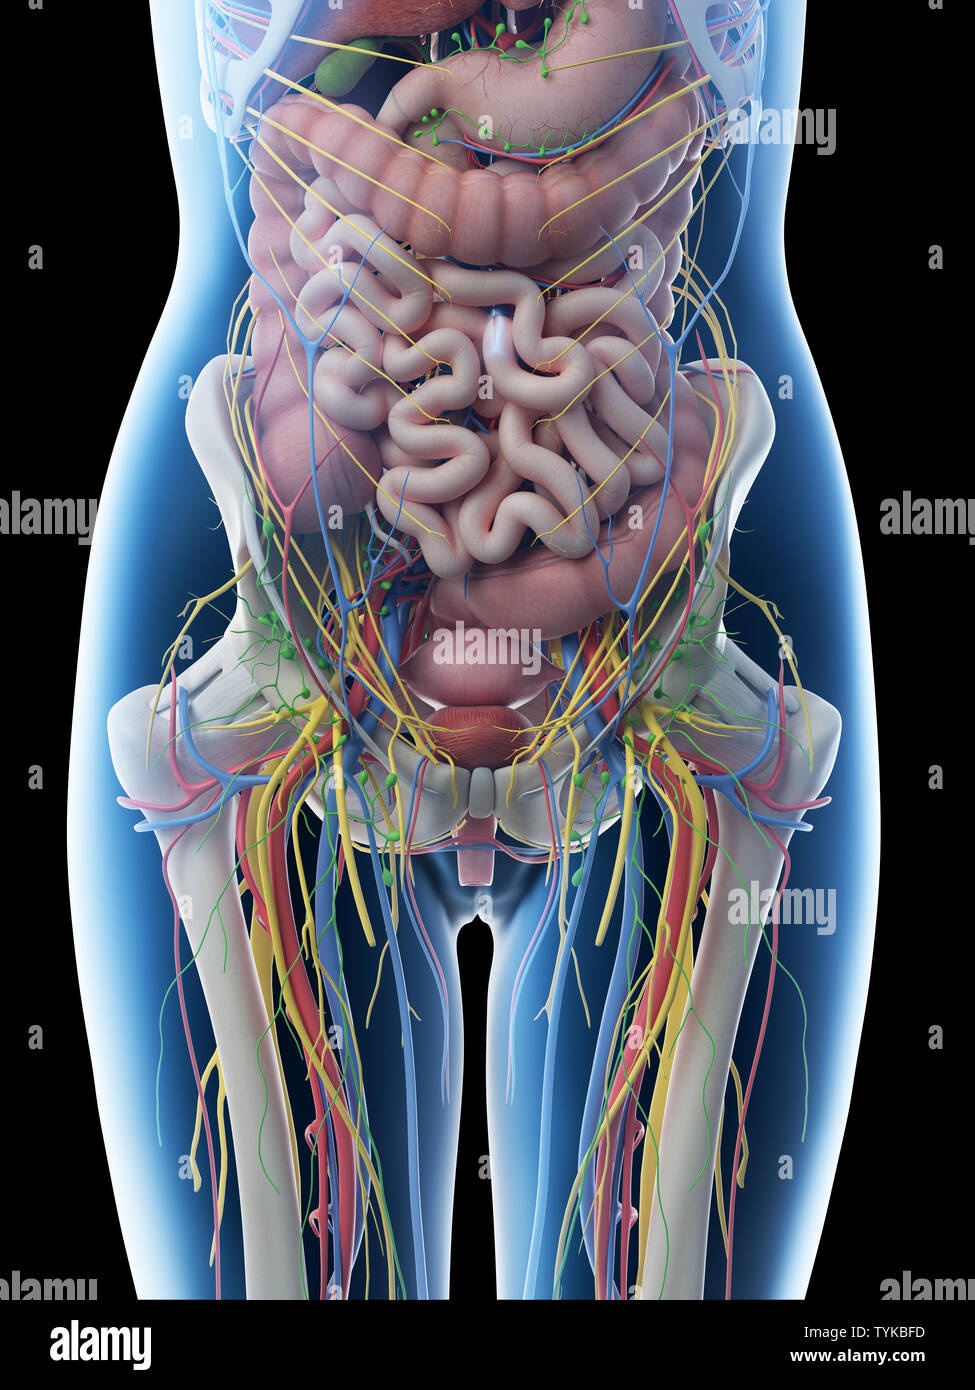

Organes abdominaux et pelviens féminins, illustration. Banque D'Imageshttps://www.alamyimages.fr/image-license-details/?v=1https://www.alamyimages.fr/organes-abdominaux-et-pelviens-feminins-illustration-image600036390.html

Organes abdominaux et pelviens féminins, illustration. Banque D'Imageshttps://www.alamyimages.fr/image-license-details/?v=1https://www.alamyimages.fr/organes-abdominaux-et-pelviens-feminins-illustration-image600036390.htmlRF2WT60F2–Organes abdominaux et pelviens féminins, illustration.